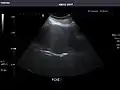

Abdominal ultrasonography (also called abdominal ultrasound imaging or abdominal sonography) is a form of medical ultrasonography (medical application of ultrasound technology) to visualise abdominal anatomical structures. It uses transmission and reflection of ultrasound waves to visualise internal organs through the abdominal wall (with the help of gel, which helps transmission of the sound waves). For this reason, the procedure is also called a transabdominal ultrasound, in contrast to endoscopic ultrasound, the latter combining ultrasound with endoscopy through visualize internal structures from within hollow organs.

Ultrasonography of the kidneys is essential in the diagnosis and management of kidney-related diseases. The kidneys are easily examined, and most pathological changes in the kidneys are distinguishable with ultrasound.[7]

Advantages of ultrasound imaging of abdominal structures are that the procedure can be performed quickly, bed-side, involves no exposure to X-rays (which makes it useful in pregnant patients, for example) and is inexpensive compared to other often-used techniques such as computed tomography (CT scan) of the abdomen. Disadvantages are troublesome imaging if a lot of gas is present inside the bowels, if there is a lot of abdominal fat, and that the quality of the imaging depends on the experience of the person performing it.